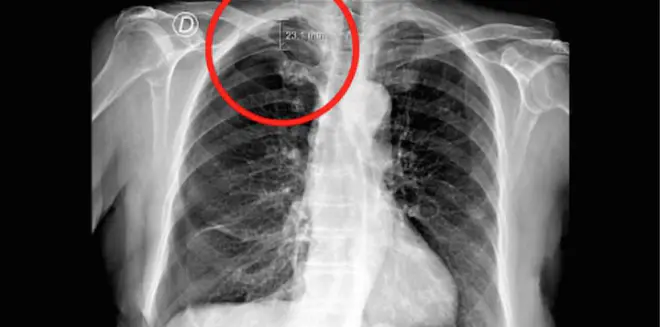

Le pneumothorax est mis en évidence dans le cercle rouge. Il correspond à une poche d'air de 23 mm entre le poumon et la cage thoracique.

Le pneumothorax est mis en évidence dans le cercle rouge. Il correspond à une poche d'air de 23 mm entre le poumon et la cage thoracique.  —  Crédits Photo : © Costa Corado et al., 2019, BMJ Case Reports

Deux jours plus tôt, cette patiente a effectué une séance d’acupuncture destinée à soulager un mal de dos chronique. Pendant la consultation, elle ressent une douleur aiguë et soudaine au niveau de l’épaule droite quand le praticien lui insère une aiguille dans la région scapulaire, située entre l’omoplate, les cervicales et la clavicule. Mais la douleur ne passe pas. Elle consulte donc son médecin généraliste et effectue une radio thoracique. Cet examen révèle un pneumothorax du côté droit, c’est-à-dire la présence d’air entre le poumon et la cage thoracique sur une hauteur de 23 millimètres.